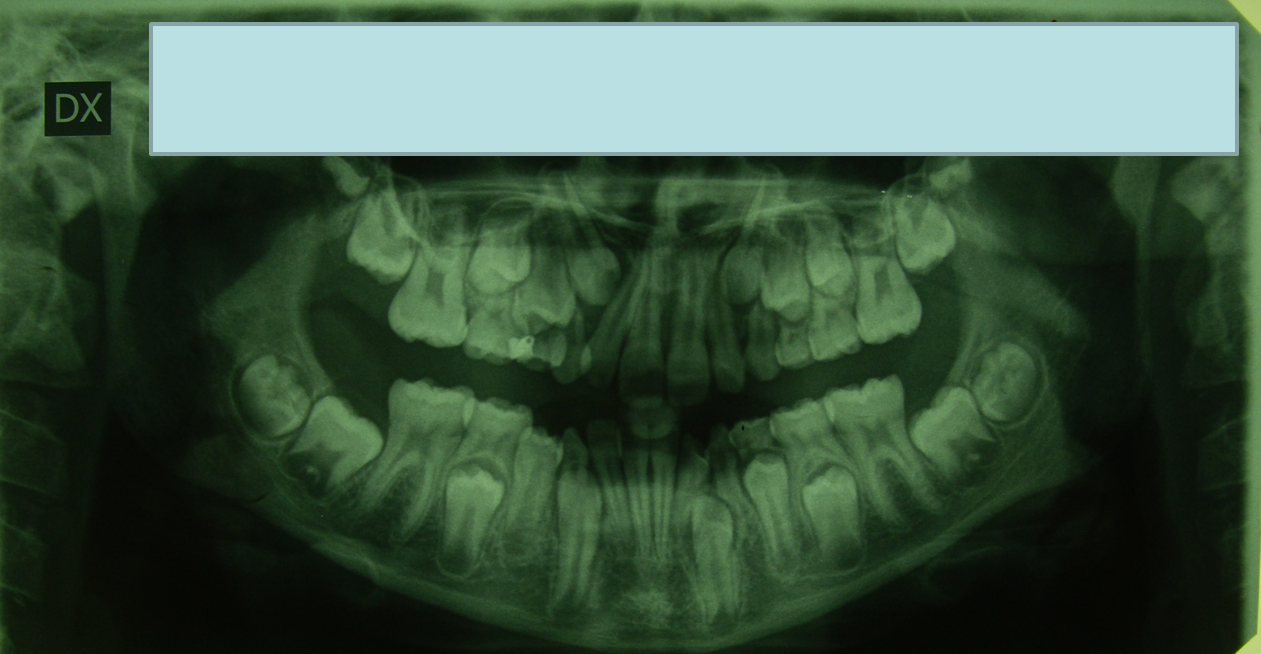

Talvolta in dentizione mista si può trarre beneficio dall'estrazione dei molari decidui per favorire il parziale miglioramento dell'affollamento anteriore, le apparecchiature a bassa frizione permettono poi di risolvere del tutto l'affollamento giocando sulle inclinazioni vestibolari delle corone.

Minimo stripping sul gruppo anteriore inferiore, in questo caso.